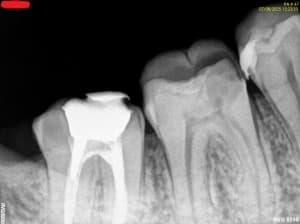

20-04-2021 Panoramique Début.JPG

10-07-2025 Panoramique Fin.JPG